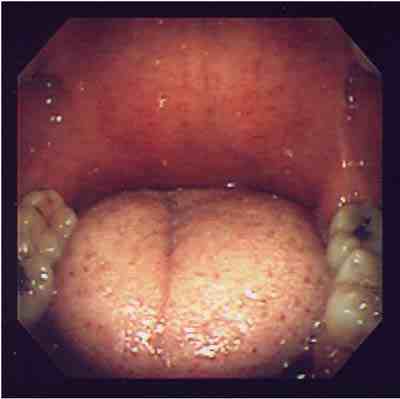

無呼吸の原因と考えられる扁桃肥大によるのどの狭窄に対し,扁桃摘出術を行い,

軟口蓋低位と口蓋垂の伸長に対し,UPP(uvulopalatoplasty)を行った例。

手術前手術後

のどの奥が広くなっているのがわかります。